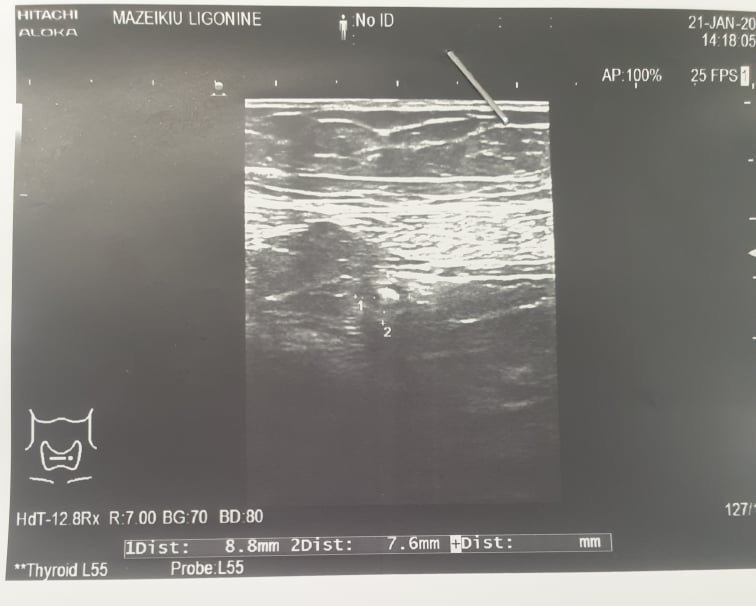

Женщина 62 года, заболела позавчера, вчера находилась в хирургическом отделении, острая абдоминальная патология была исключена. Направлена на УЗИ семейным доктором, так как боли в животе сохраняются.

Живот болезненный в правой подвздошной области.

Аппендикс менее 7 мм в диаметре, с жидким содержимым, не компрессируется, не виден отек брыжейки. Резкая болезненность при снятии датчика.

Высказано подозрение на острый аппендицит.

Прооперирована, со слов хирургов острый флегмонозный аппендицит.

Как видим на фото, диаметр аппендикса небольшой, удивляет брыжейка аппендикса.

Гистология: Острый флегмонозный аппендицит, местный серозит.